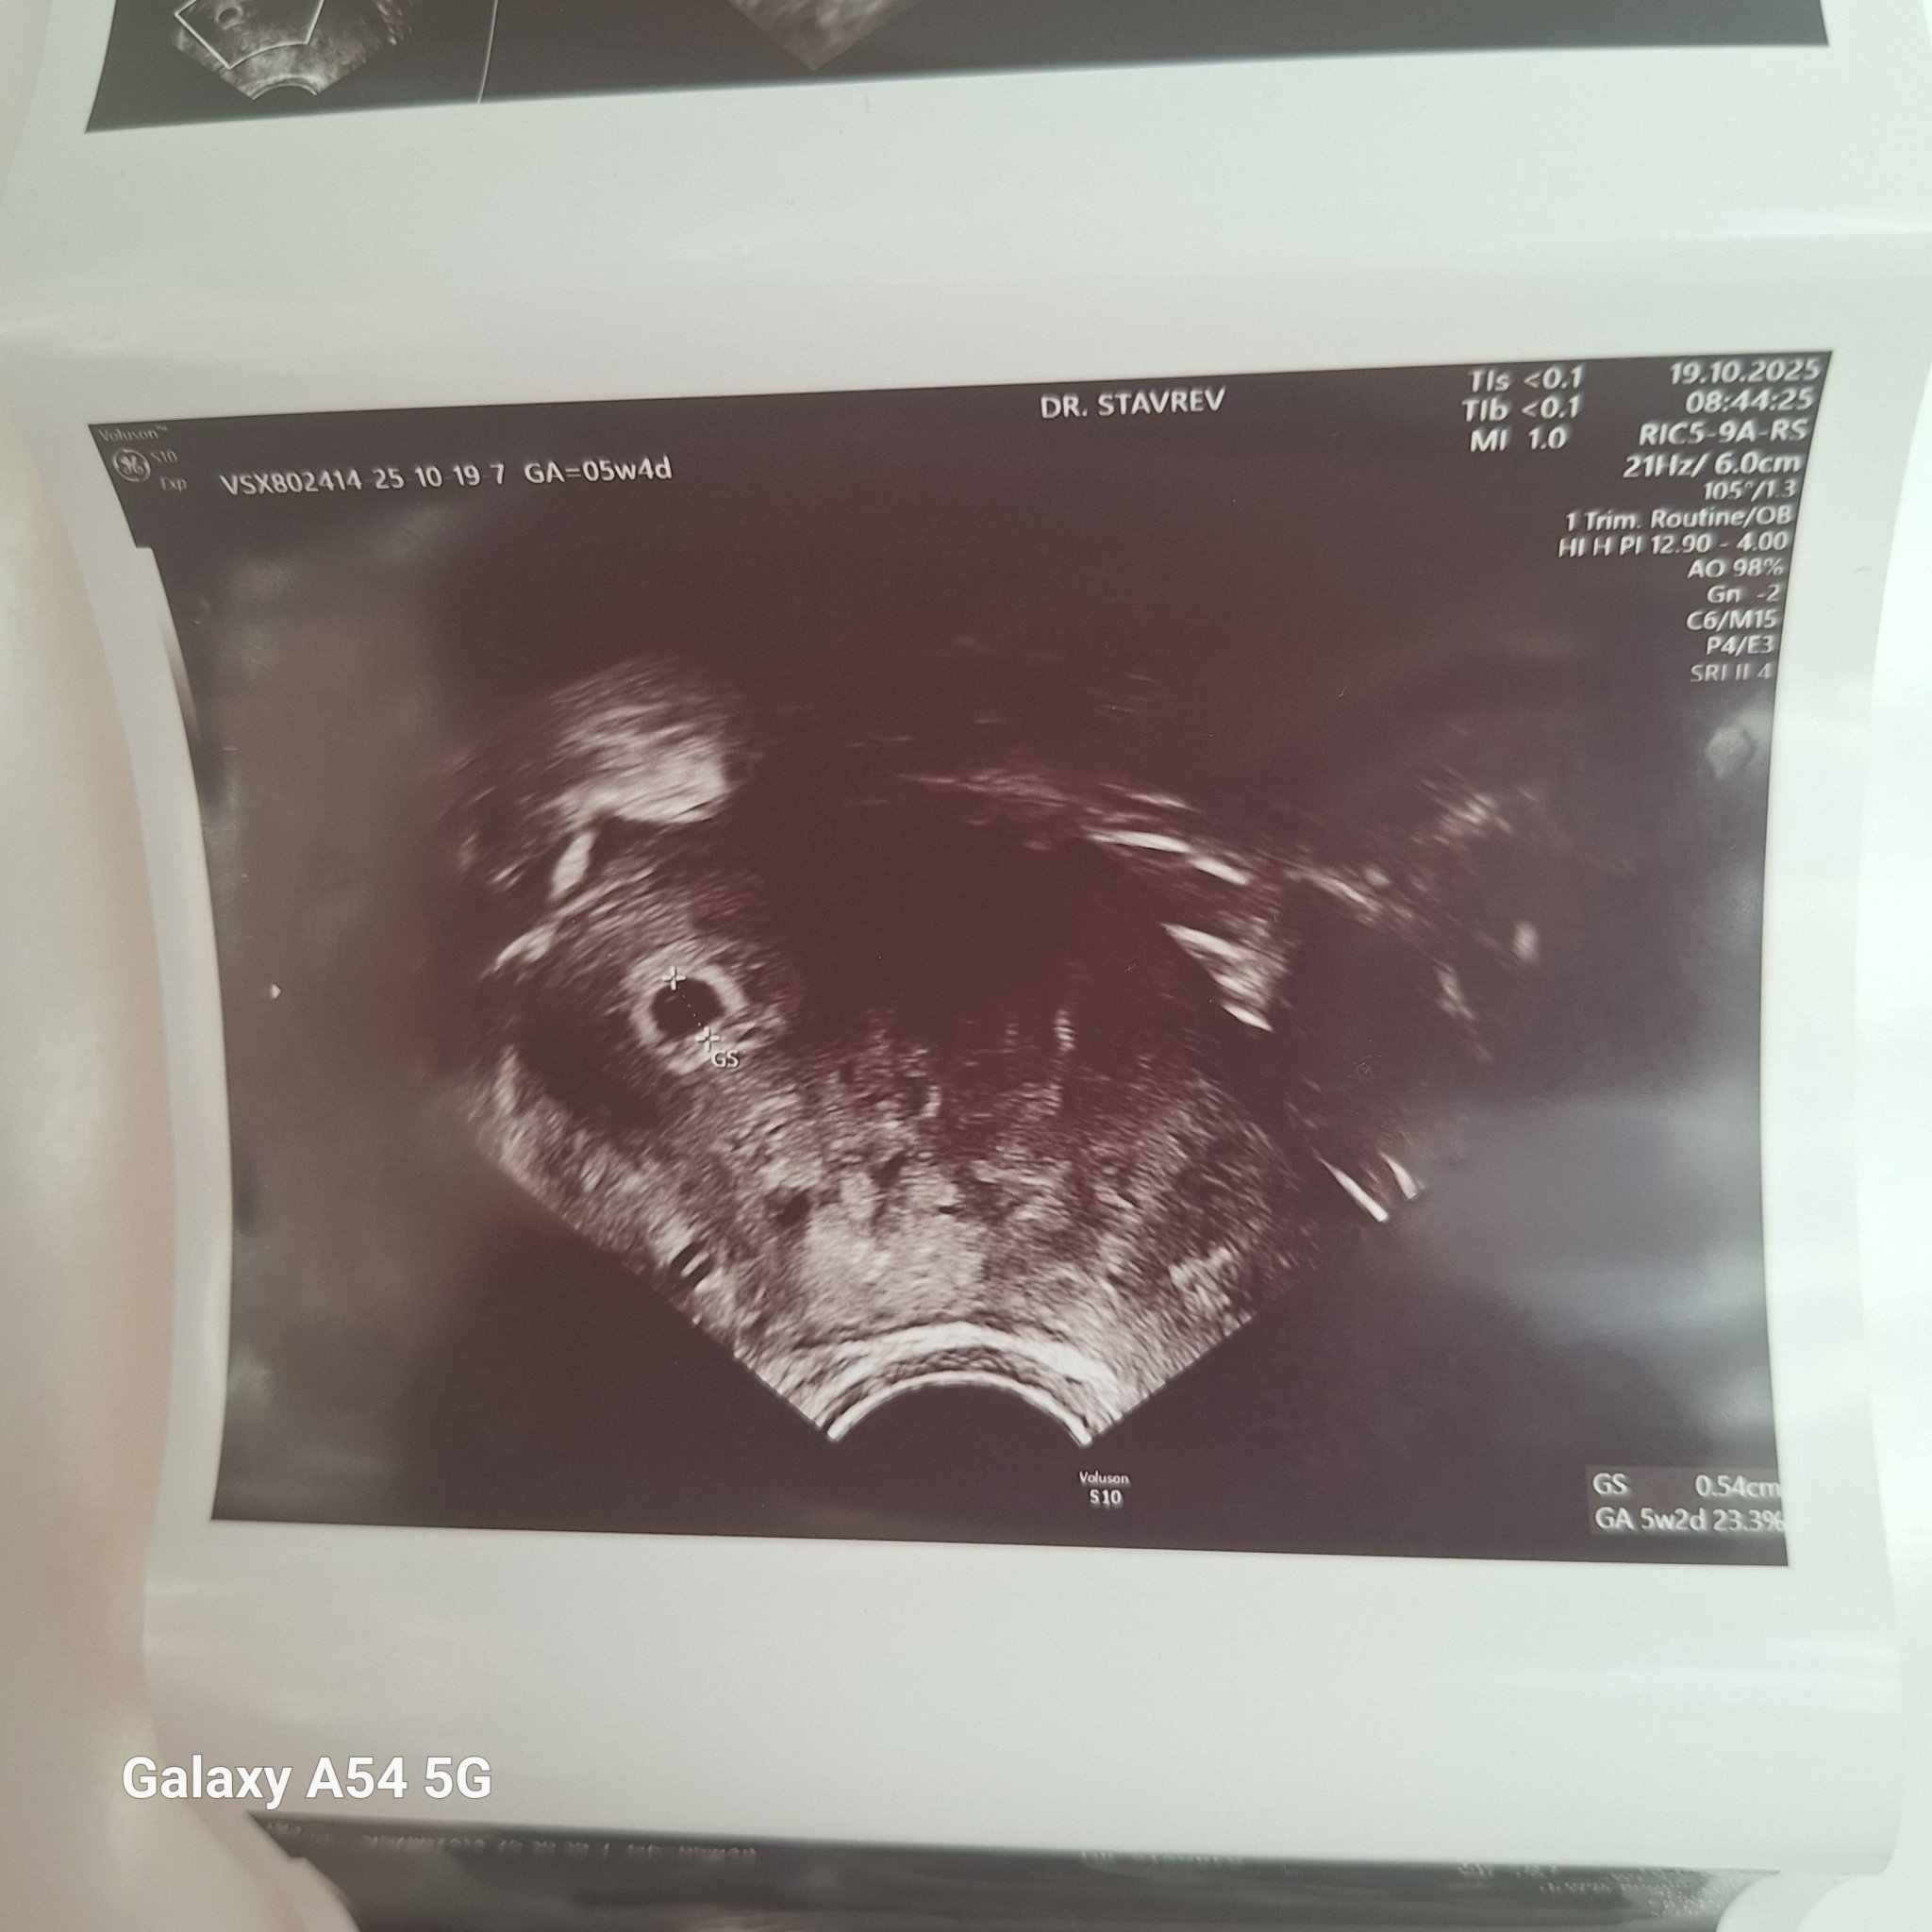

Какво представлява изображението от ехографията на 5-седмична и 2-дневна бременност?